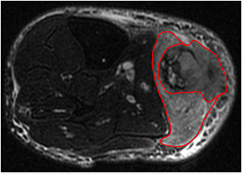

Contours defining the 3D tumour region for each patient were manually drawn slice-by-slice on T2FS scans by an expert radiation oncologist. For patients with visible edema in the vicinity of the tumours (n = 32), two contours were drawn: one incorporating the visible edema and one excluding it, as shown in figure 2. Contours were propagated to FDG-PET and T1 scans using rigid registration with the commercial software MIM® (MIM software Inc., Cleveland, OH). The results presented in this work were obtained from texture analysis performed on the volume of interest of each patient as defined by the contour containing no edema.

Figure 2. Example of soft-tissue sarcoma tumour volume definition performed on the T2-weighted fat-saturated scan of a patient of the LungMets group. The inner contour exclude visible edema in the vicinity of the tumour.